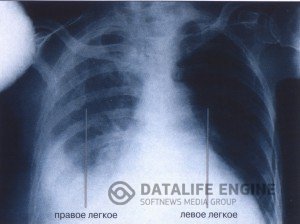

Легочно-сердечная недостаточностьДыхательная и легочно-сердечная недостаточность возникают от многих причин. На первом месте стоят такие... Легочно-сердечная недостаточностьДыхательная и легочно-сердечная недостаточность возникают от многих причин. На первом месте стоят такие...